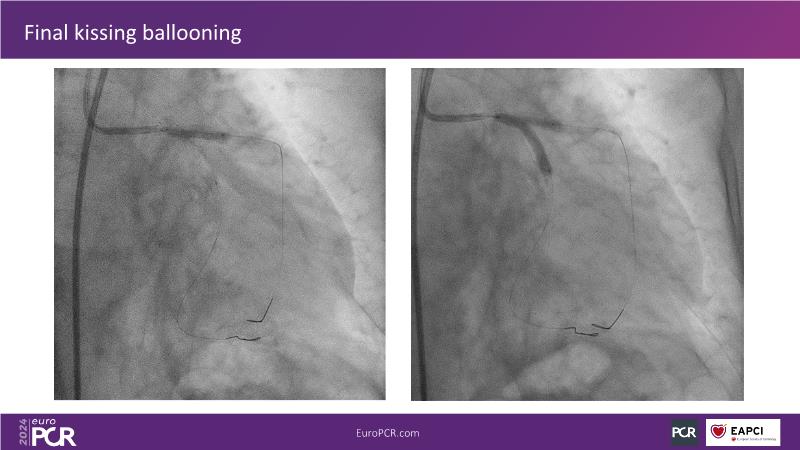

From innovation to reality: the impact of Cre8 EVO technology on complex PCI

This session is a good opportunity to delve into the contemporary technical and clinical complexities surrounding complex PCIs in challenging patient cases. Explore the necessary tools and treatment strategies to enhance peri-procedural and long-term clinical outcomes, and follow discussions on the unique technologies of Cre8 EVO in complex PCI scenarios.